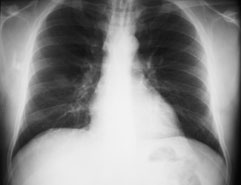

Ein 41-jähriger Mann sucht Sie auf, weil er zum dritten Mal in diesem Winter erkältet ist und dieses Mal sogar mit Fieber. Er gibt ausserdem an, etwas trockenen Husten zu haben. Ausserdem besteht seit Wochen eine Sinusitis, die nicht so recht abheilen will.

Gewichtsverlust wird verneint. Der Patient ist Nichtraucher und fühlte sich bis anhin gesund.

Die Lungenperkussion und -auskultation ist unauffällig. Das Labor zeigt eine Leukozytose ohne Linksverschiebung und ein CRP von 97 mg/dl. Hier das Röntgenbild der Lunge:

Thorax pa

Thorax seitlich

Welche Befunde fallen Ihnen auf?

Es ist klar, dass aufgrund dieses Befundes keine Diagnose gestellt werden kann. Welche Diagnose ist aufgrund der Klink und des radiologischen Befundes am wahrscheinlichsten?